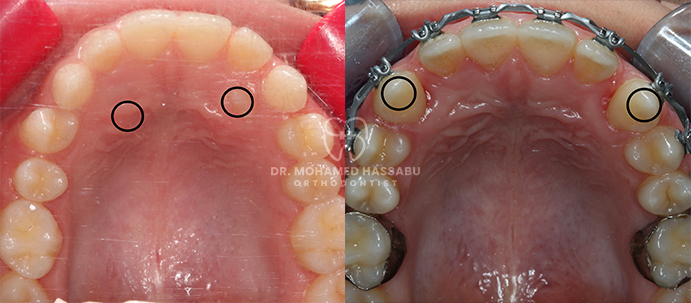

Traditional Braces:

Traditional braces, which have been proven effective over time, use metal brackets and wires to gently shift teeth into their correct places. Your child can add colorful bands to personalize their braces and make them uniquely theirs.

Customized Treatment Plan:

Based on the evaluation, we will create a personalized treatment plan that addresses your child’s specific orthodontic needs and preferences.

Achieving a Beautiful Smile:

As your child’s teeth gradually align, you’ll witness their confident and beautiful smile emerge.